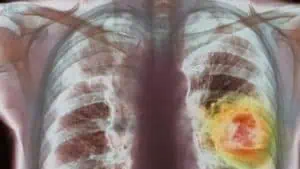

В България има „драматично увеличение“ на броя на новите случаи на онкологични заболявания, каза д-р Нилс Уилкинг от Каролинския институт в Стокхолм. На кръгла маса у нас той представи сравнителен доклад за достъпа на пациентите до онкологични лекарства в Европа. В другите държави също има нарастване на новите случаи, но България е с едни от най-високите нива. Шведският лекар отчете, че у нас има проблеми с диагностиката, особено на по-възрастните пациенти.